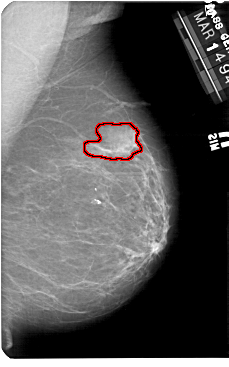

A_1182_1.RIGHT_CC

RIGHT_CC LINES 5491 PIXELS_PER_LINE 3121 BITS_PER_PIXEL 12 RESOLUTION 43.5 OVERLAY

FILE: A_1182_1.RIGHT_CC.OVERLAY

TOTAL_ABNORMALITIES 1

ABNORMALITY 1

LESION_TYPE MASS SHAPE IRREGULAR MARGINS ILL_DEFINED

ASSESSMENT 4

SUBTLETY 5

PATHOLOGY MALIGNANT

TOTAL_OUTLINES 1

BOUNDARY